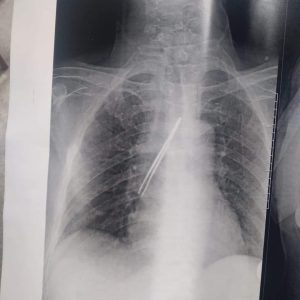

نجح فريق جراحي بقسم جراحة القلب والصدر بمستشفى بنها الجامعي بمحافظة القليوبية، في استخراج “ملقاط شعر”، من القصبة الهوائية لمريض يعاني من شق حنجري قديم، وأثناء قيامه بتنظيف فتحة الشق الحنجري بطريقة غير طبية وغير صحيحة باستخدام الملقاط ملفوف بمناديل ورقية، سقط منه وابتلعه ودخل لفتحة القصبة الهوائية.

وأوضح مستشفى بنها الجامعي، فى بيان له، أنه جرى الآن استخراج “ملقاط شعر” من القصبة الهوائية لمريض يعاني من شق حنجري قديم، وبينما يقوم بتنظيف فتحة الشق الحنجري بطريقة غير طبية وغير صحيحة باستخدام ملقاط ملفوف بمناديل ورقية اتشفط منه الملقاط ودخل لفتحة القصبة الهوائية.

وتابع المستشفى، أنه حضر المريض للقسم في حالة اختناق، وتم دخوله العمليات فورا، حيث نجح الدكتور باسم مفرح الأستاذ المساعد بالقسم، وبمعاونة الدكتور أحمد الخضري مدرس مساعد التخدير، من استخراج “الملقاط”، وخرج المريض بسلامة الله من العمليات ويخضع لاستكمال علاجه بالقسم لحين تماثله الكامل للشفاء.